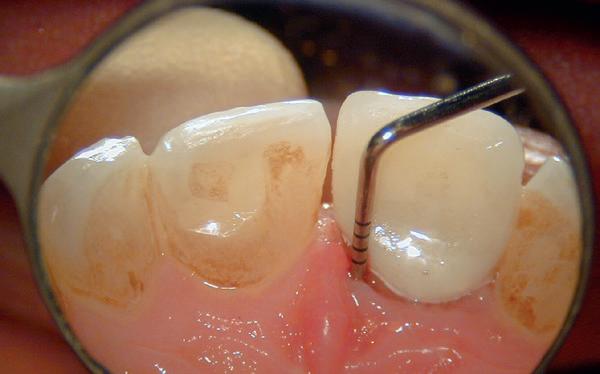

Een 47-jarige collega presenteert zich in onze verwijspraktijk voor endodontie. Hij heeft enige tijd geleden zijn kroon op de 11 laten vervangen (afbeelding 1). Omdat er geen klinische en röntgenologische aanwijzingen waren voor een periapicale laesie of een insufficiënte wortelkanaalbehandeling van de 11, werd besloten de endo, die dateerde van meer dan 30 jaar geleden, niet te reviseren (afbeelding 2). Tijdens een routinematige gebitsreiniging constateert zijn mondhygiënist een pocket van 7 mm aan de mesiopalatinale zijde van 11 (afbeelding 3). De nieuwe kroon wordt tijdelijk gecementeerd, en omdat

1: Klinische foto van bovenfront

2: Röntgenfoto van 11 met zilverstift sectie

3: Pocket palatinaal 11